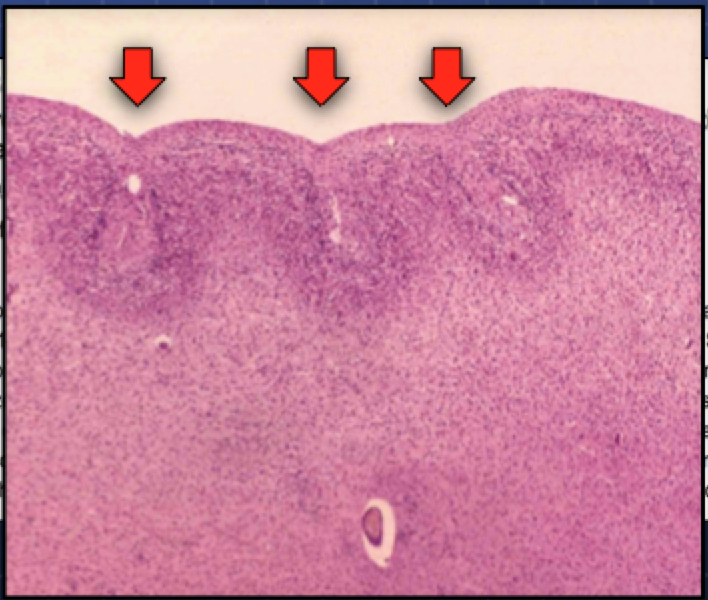

Polymicrogyria, which means “many small gyri”, appears to be overrepresented in autism as well. Below you can see a micrograph of the small gyri, with their shallow sulci (valleys) and what usually looks like a fusing of the uppermost layer (Layer I) of the neocortex (arrows).